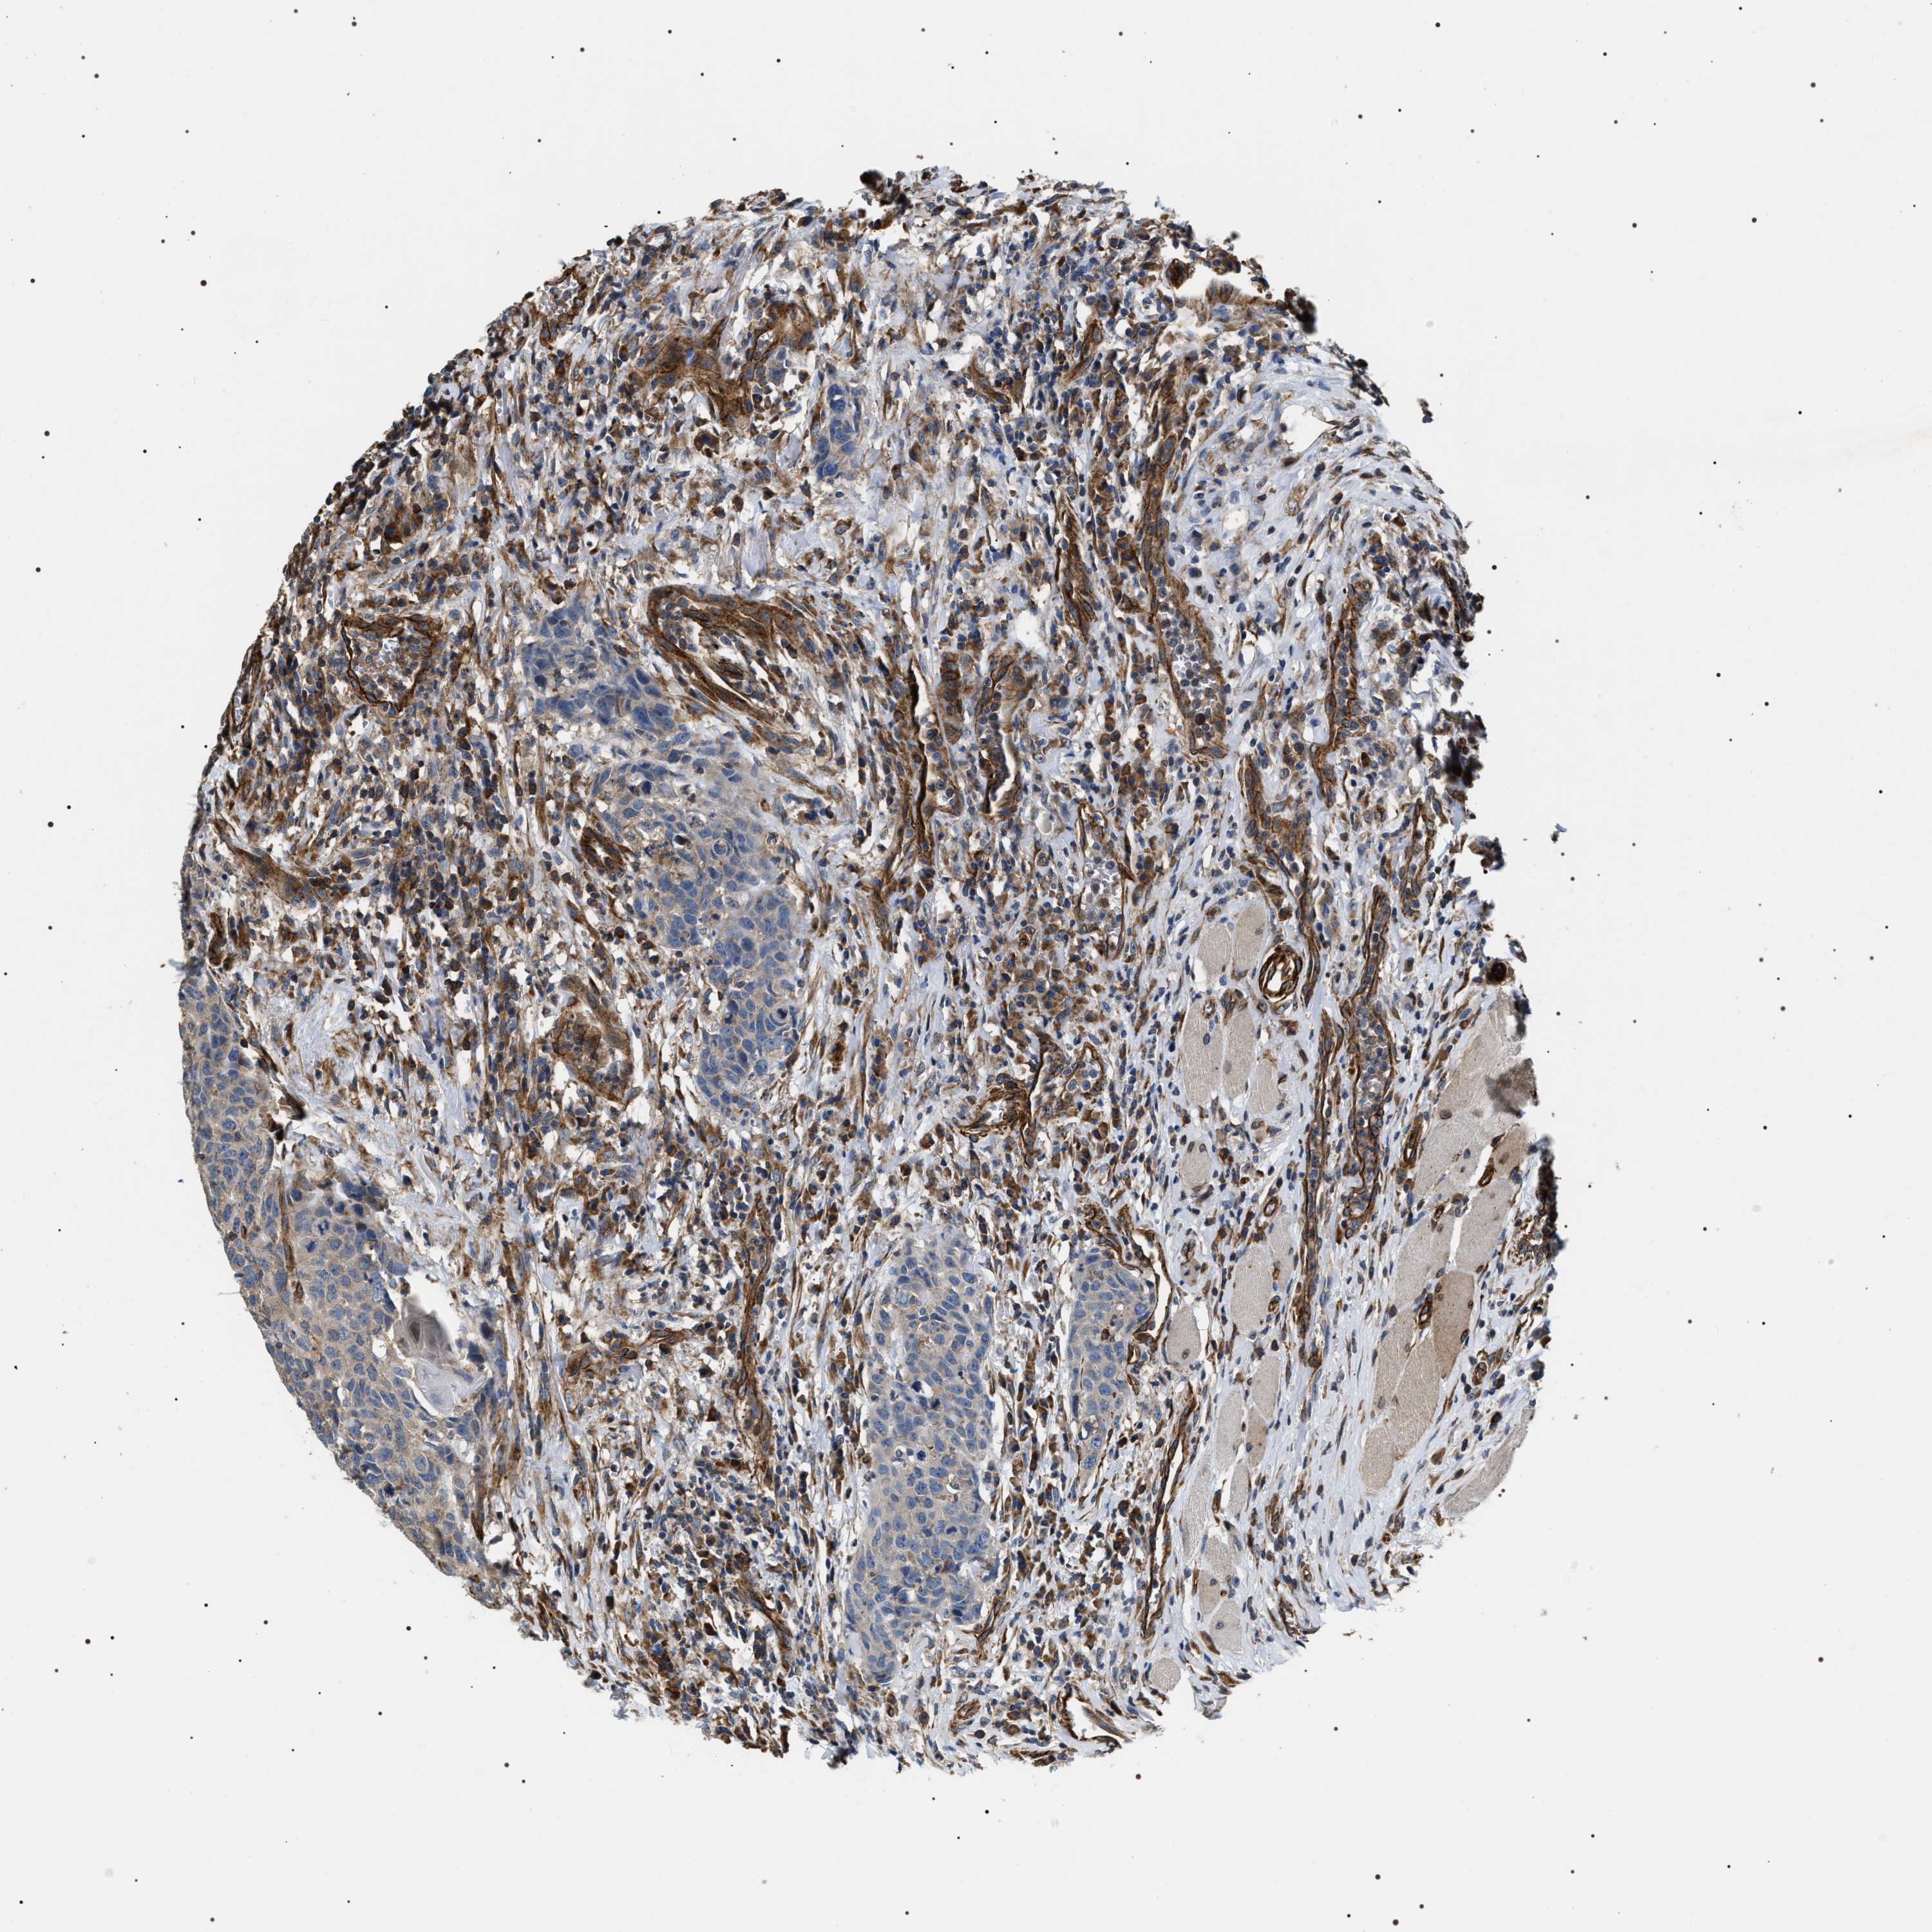

HEAD AND NECK CANCER - Protein expressioni

A mouse-over function shows sample information and annotation data. Click on an image to view it in a full screen mode. Samples can be filtered based on level of antibody staining by selecting one or several of the following categories: high, medium, low and not detected. The assay and annotation is described here.

Antibody stainingi

Antibody staining in the annotated cell types in the current human tissue is reported as not detected, low, medium, or high, based on conventional immunohistochemistry profiling in selected tissues. This score is based on the combination of the staining intensity and fraction of stained cells.

Each image is clickable and will lead to virtual microscopy that enables deeper exploration of all samples and also displays staining intensity scores, fraction scores and subcellular localization as well as patient and tissue information for each sample.

Antibody HPA020386

Squamous cell carcinoma, NOS

Squamous cell carcinoma, metastatic, NOS